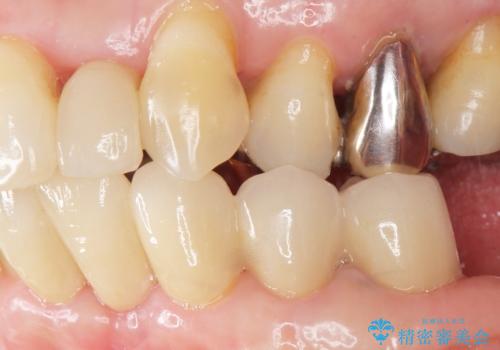

気にされていた前歯と奥歯の動揺がなくなったことと自然な仕上がりに喜んで頂けました。

クラウンの種類:オールセラミッククラウン スタンダード

また、咬み合わせが反対になっている上の前歯(左上2)も補綴で形を変えることにより、咬合を改善しました。